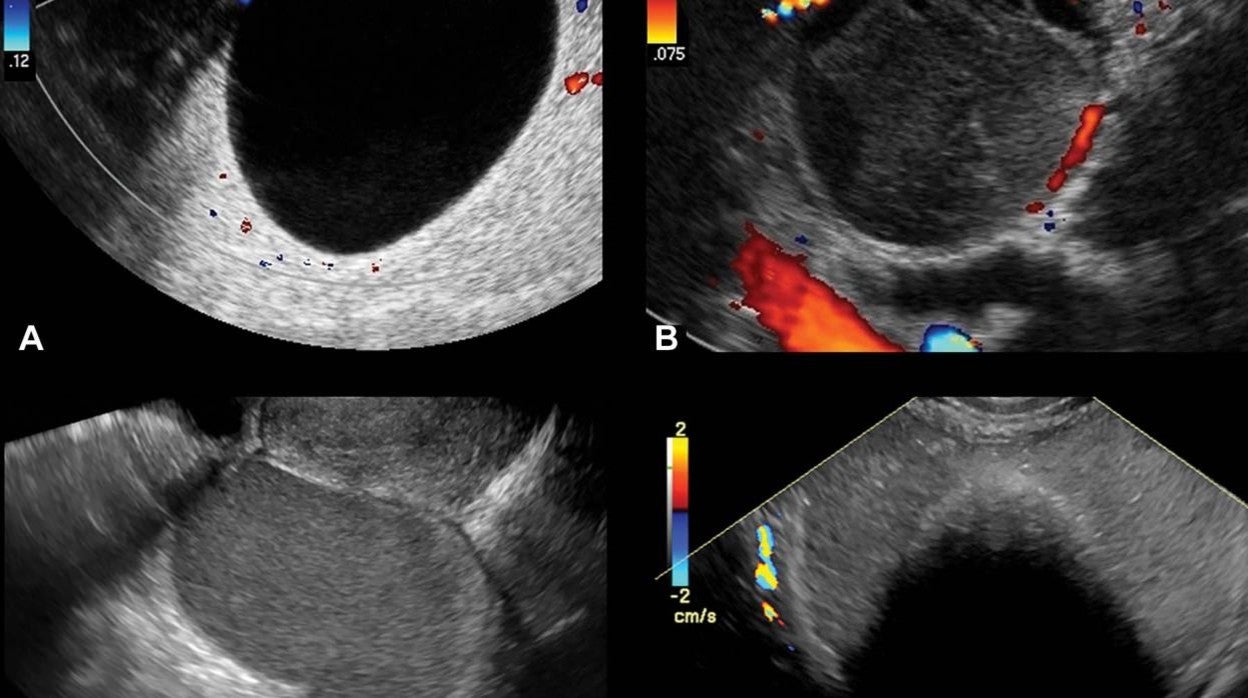

UlImágenes transvaginal representativas de lesiones clásicas Sociedad Radiológica de América del Norte

En el nuevo estudio, Gupta y sus colegas evaluaron un método que usa imágenes de ultrasonido para clasificar las estos quistes en una de dos categorías: clásicos o no clásicos.

Las lesiones clásicas son las que se detectan comúnmente, como los quistes llenos de líquido, que tienen un riesgo muy bajo de malignidad. Las lesiones no clásicas incluyen lesiones con un componente sólido y flujo sanguíneo detectado en la ecografía Doppler. Un enfoque clásico versus no clásico para estas lesiones podría ayudar a los radiólogos en una práctica clínica ocupada a evaluar más rápidamente una lesión.

La frecuencia de malignidad fue inferior al 1% en lesiones con características ecográficas clásicas. Por el contrario, las lesiones que tenían un componente sólido con flujo sanguíneo tenían una frecuencia de malignidad del 32 % en el grupo de estudio general y del 50 % en los participantes del estudio que tenían más de 60 años .

«Si tiene algo que sigue los patrones de imágenes clásicos descritos para estas lesiones, entonces el riesgo de cáncer es realmente bajo», afirmó Gupta. «Si tiene algo que no tiene una apariencia clásica, entonces la presencia de componentes sólidos y, en particular, la presencia de flujo sanguíneo Doppler es realmente lo que aumenta el riesgo de malignidad».